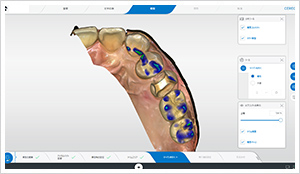

小型カメラでお口の中をスキャン(撮影)します。

従来の型取りの不快感を味わうことなく、

お口の中の歯がモニターに映し出されます。

これは実際に、左上インレーの形成を行い

口腔内スキャンした画像です。

モニター上で、あらゆる角度から噛み合う部分や形を微調整して患者様固有の理想的な歯の形を設計します。